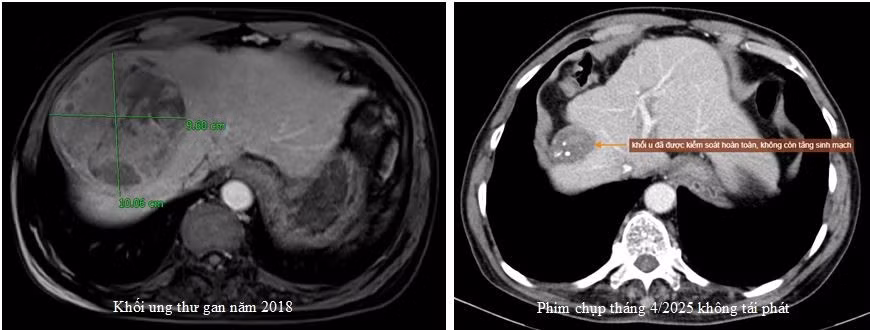

Trường hợp điển hình là người bệnh A.V.Q, 74 tuổi, ở Cẩm Khê – Phú Thọ, phát hiện ung thư gan với kích thước 10cm, đã được nút mạch sử dụng kỹ thuật TACE.

Sau 4 lần thực hiện nút mạch từ năm 2018 đến 2022, duy trì thăm khám, theo dõi thường xuyên, đến nay khối u của bệnh nhân đáp ứng tốt và teo nhỏ, không có sự tái phát - Ảnh BVCC